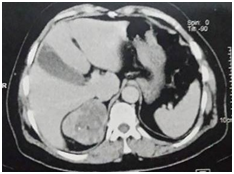

A CT scan showed a right lesional adrenal process, well confined by lobulated contours, hypodense, containing greasy spots and calcifications (Figure 1), heterogeneously enhanced after a contrastive injection (Figure 2), measuring 71×60×55mm.

Figure 1 Abdominal CT scan showing the right adrenal mass hypodense containing greasy spots.